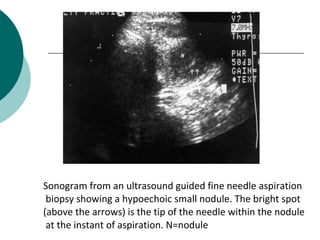

Sonogram from an ultrasound guided fine needle aspiration

biopsy showing a hypoechoic small nodule. The bright spot

(above the arrows) is the tip of the needle within the nodule

at the instant of aspiration. N=nodule